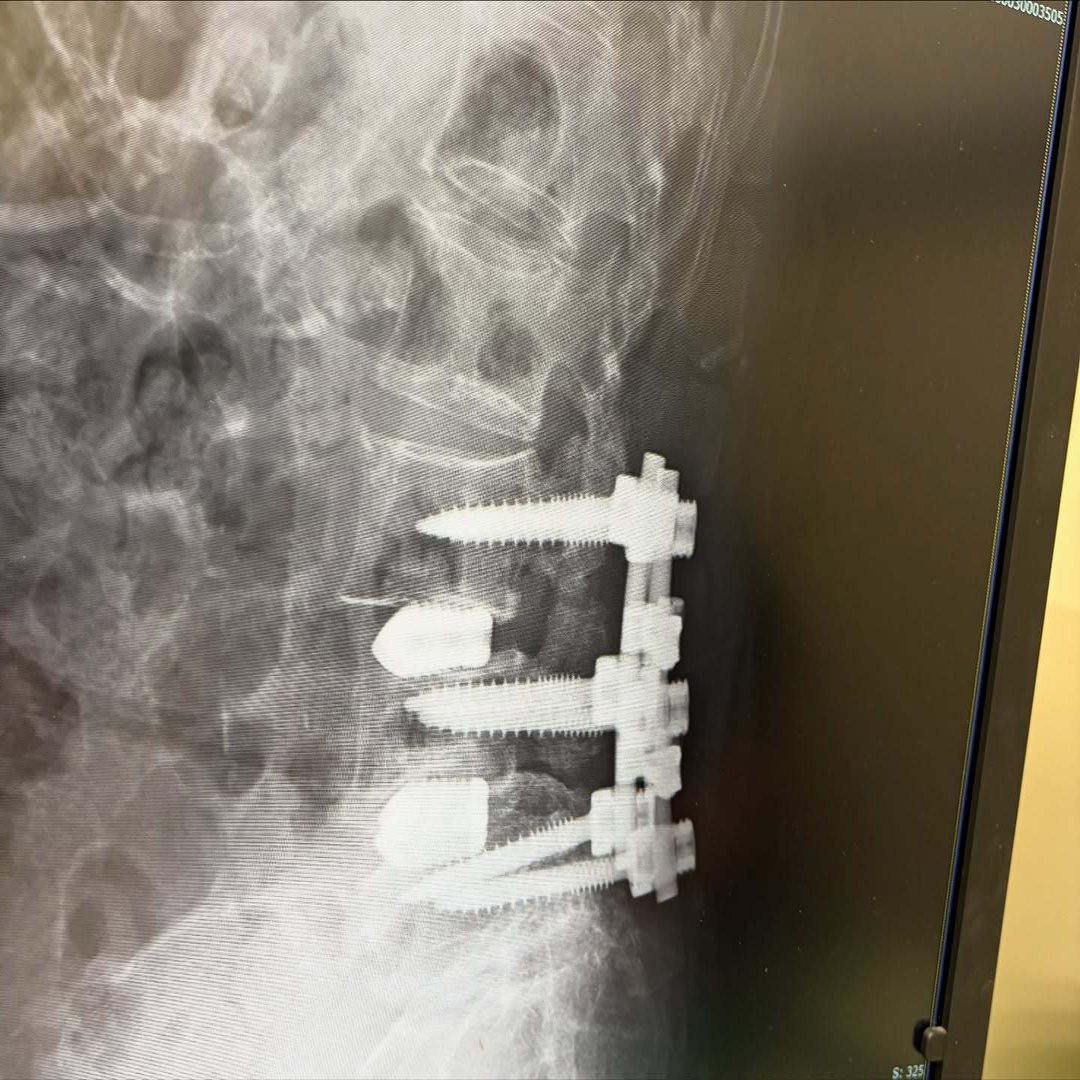

先日ガズ母の病院に付き添ってきたーー脊髄の大手術から初めての診察。

レントゲンを見せてもらったらボルトがゴッツリ背骨に打ち込まれてて、もうドン引き!「こんなにガチガチに固定してるの!?」。。。。

でも、そのおかげで痛みがすごく楽になったみたい、、、医療って本当にすごいよねー